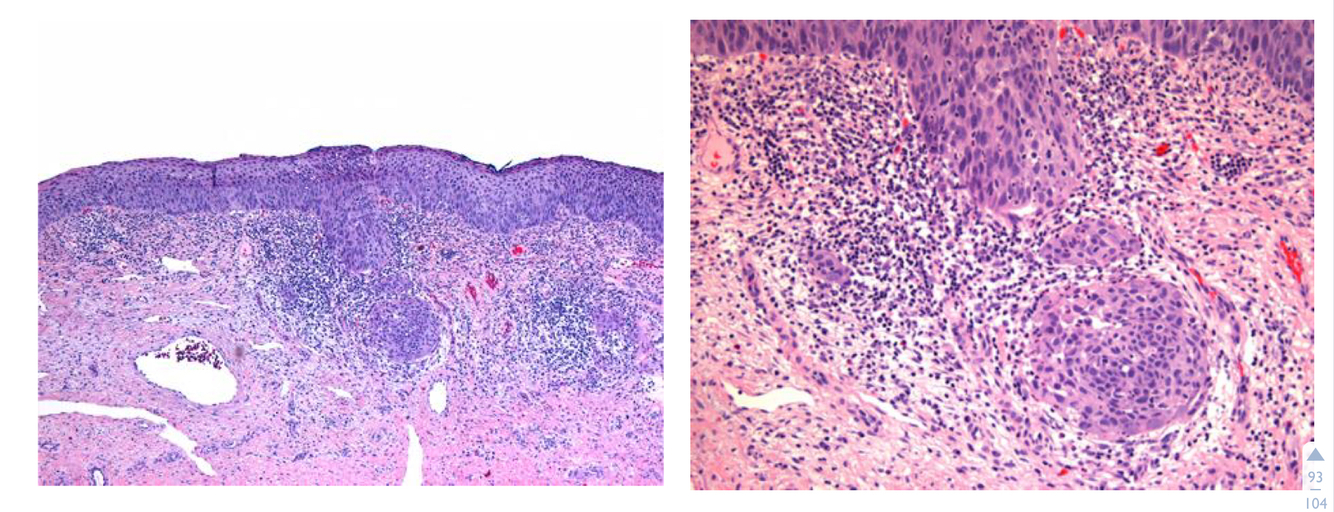

What can be seen here?

Mitotic figures

This is taken of the patient’s loop excision.

What does it show?

It shows invasive cervical carcinoma where there has been invasion of the basement membrane and suggest malignancy.

Extensive invasion to the stroma through the basement membrane